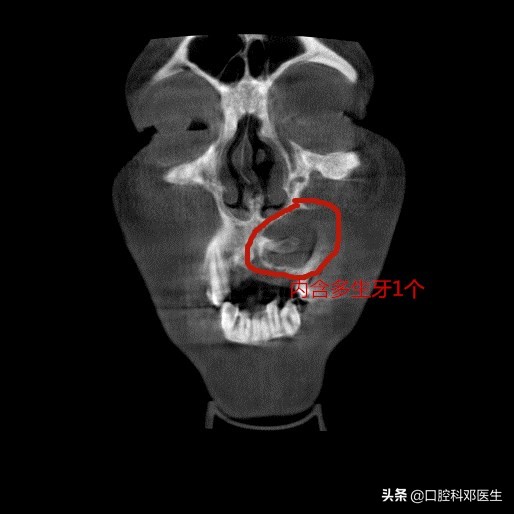

40岁严某最近20天比较苦恼,朋友们都说他脸肿了,平时也不痛不痒的,怎么脸就像吹气球样的越来越肿了呢?而且连张口都困难了。于是他来到长沙市中心医院口腔科检查,一检查牙齿和口腔都没有问题,医生建议他拍个口腔X线片看看,不照不知道,一照吓一跳,X线片显示他的左侧上颌骨已经被吃空了,必须住院进行上颌骨囊肿根治手术。

接诊的邓医生介绍:这位患者脸肿大是由于左侧上颌骨内一个埋伏多生的牙齿所引起的,由于牙齿无法正常萌出,经过时间的积累,从而诱发囊肿,囊肿一般都不痛不痒,越长越大,像鼓气球一样,逐渐破坏了周围的骨头,如破坏上颌骨前壁,就会突破至软组织,引起脸部肿大;如破坏牙槽骨,则会导致牙齿松动移位,引起牙根吸收疼痛等症状。